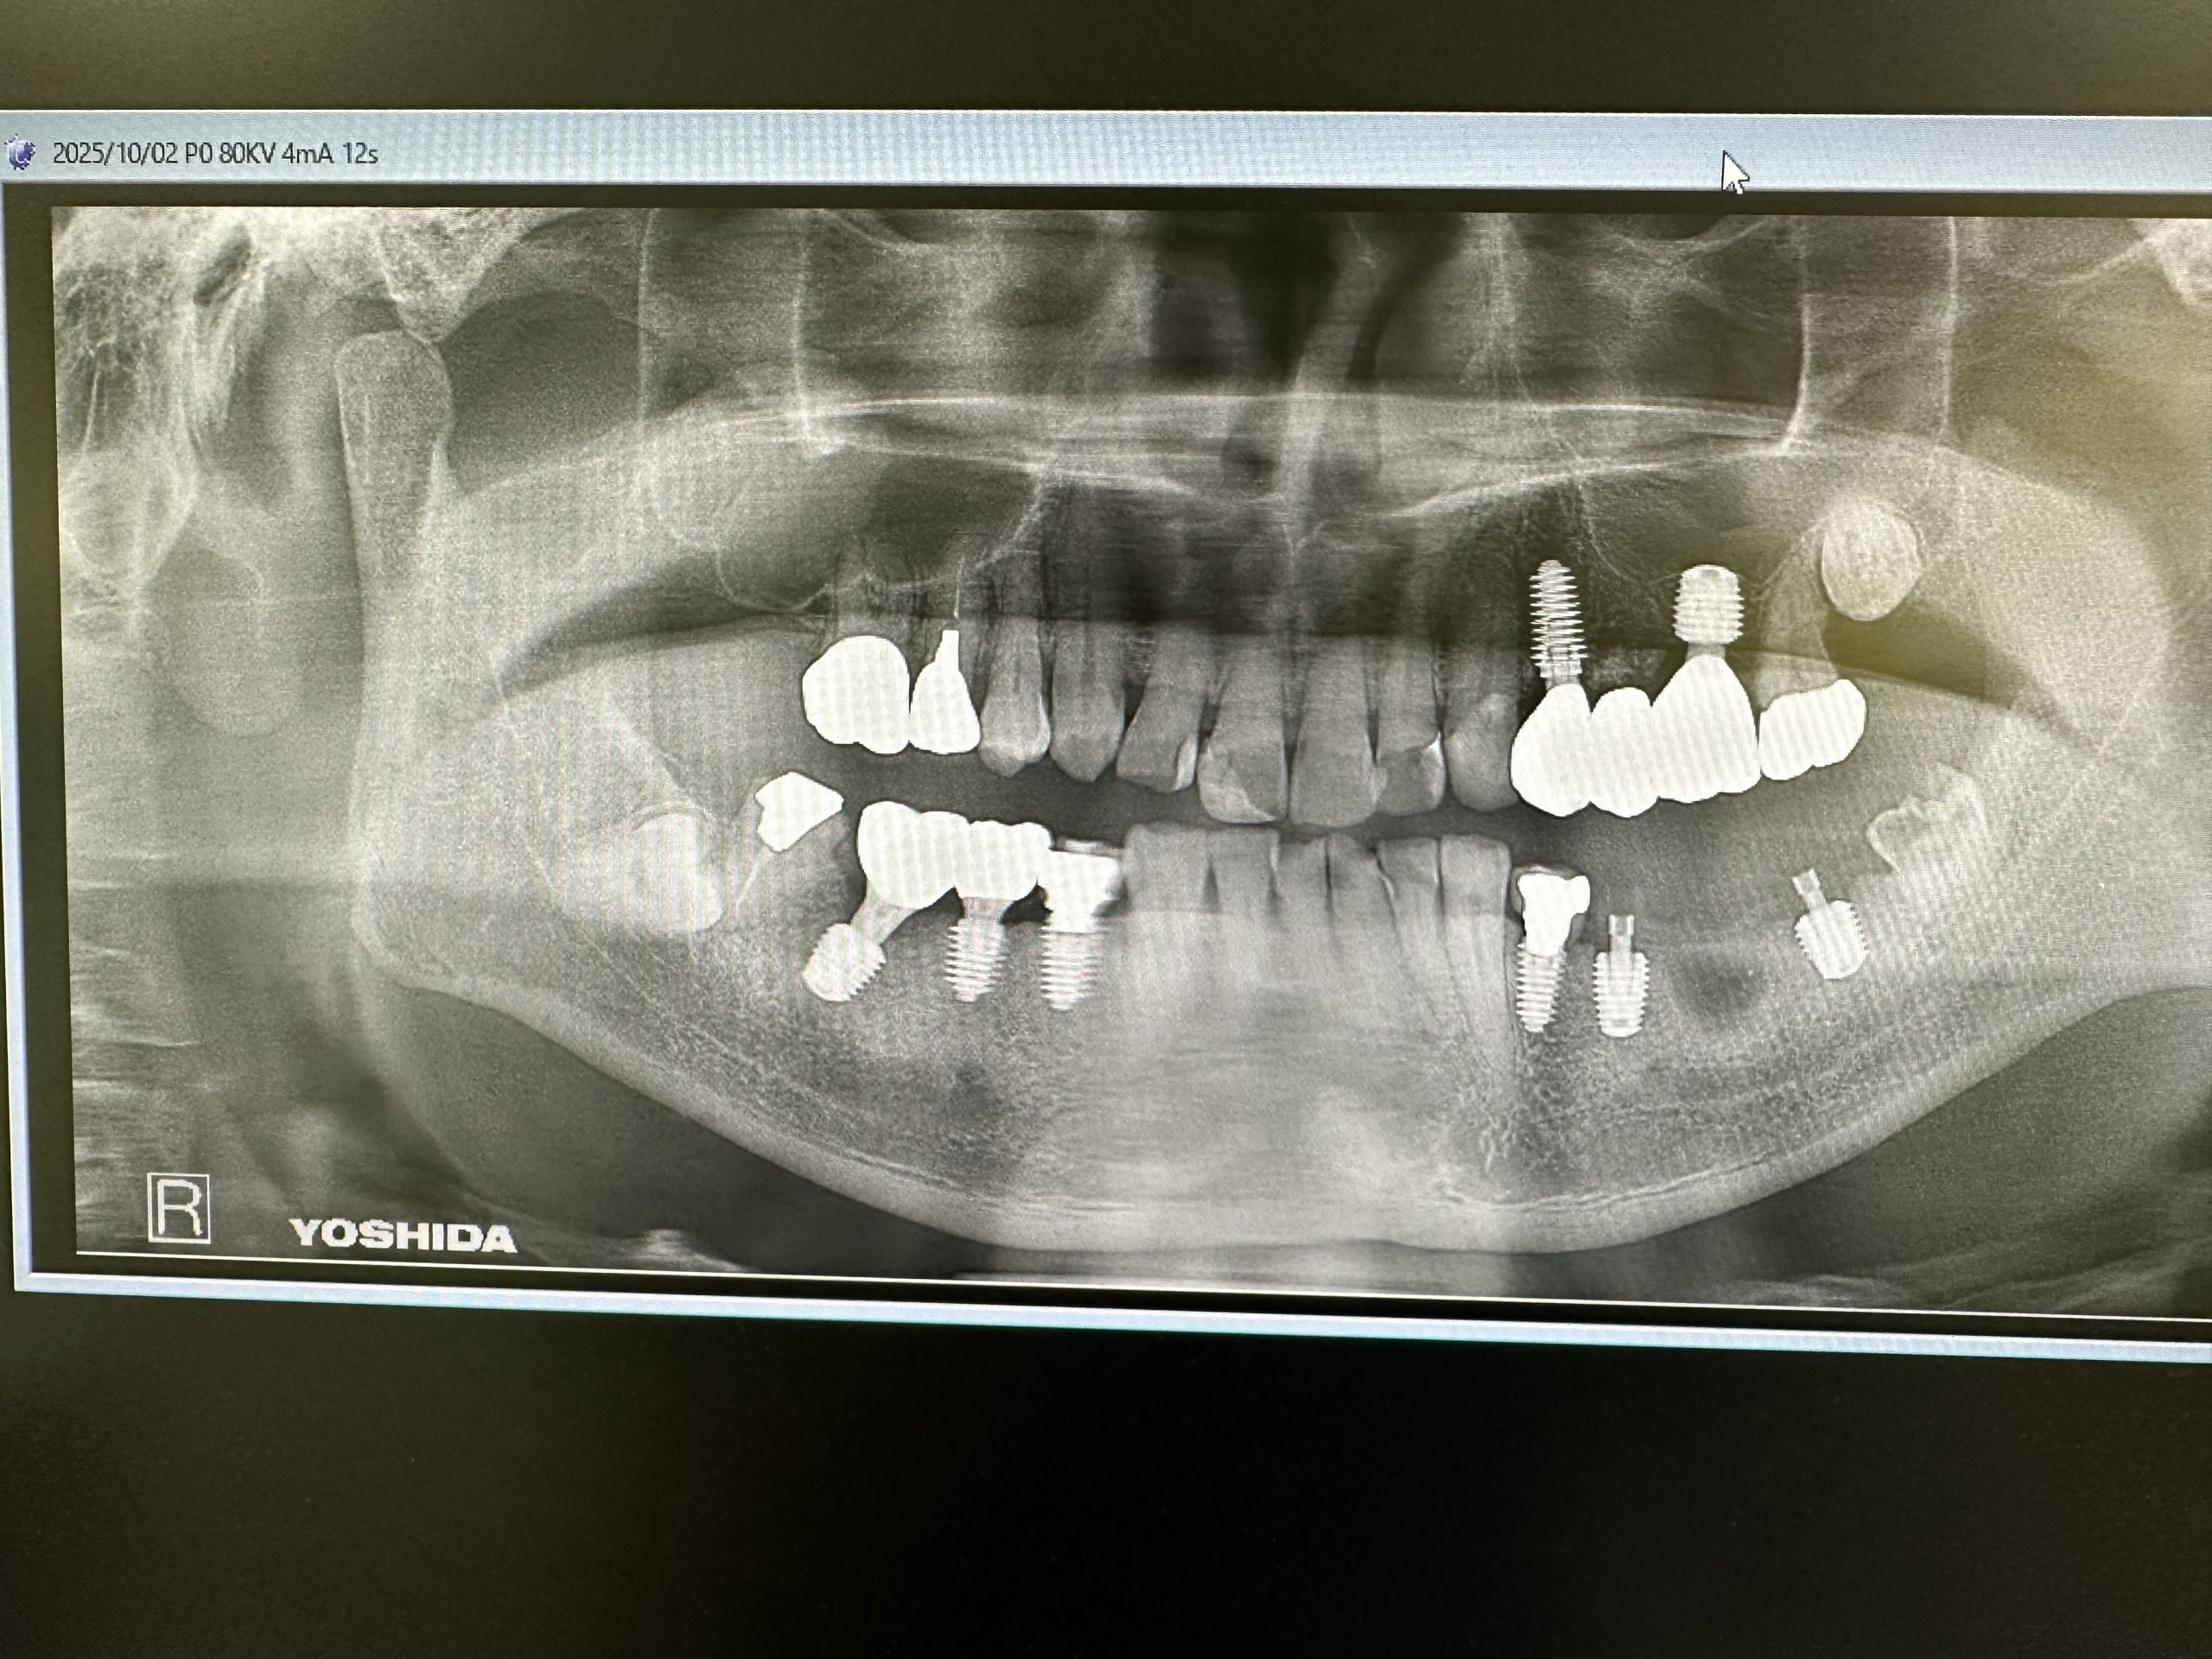

本日は午前、午後とインプラントオペあり

難なく30分で終わり

集中MAX、セプトカイン使用したが奏功しづらかった💦キシロカイよりは断然効くけど